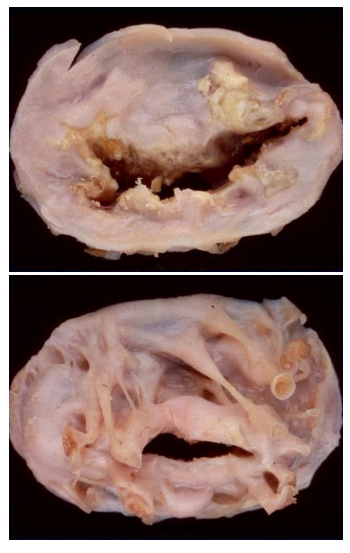

A 66-year-old diabetic man with no history of cardiac or respiratory disease is found dead in bed by his spouse. He had smoked 2 packs of cigarettes a day for 40 years. An autopsy is performed, and cross sections of the right coronary artery are examined.

A. What is the diagnosis?

B. What 2 gross findings are the basis of this diagnosis?

C. Name 4 possible acute consequences of this disease:

D. Name 4 treatment options for this disease:

A. coronary artery disease

B. thrombus, plaque –> atherosclerosis –> stenosis

C. MI, arrhythmias, angina - unstable, sudden death

D. angioplasty, thrombolytic therapy, stent, bypass